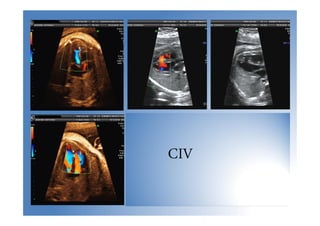

CIV

• Es la cardiopatía congénita más frecuente al

nacimiento.

• Dx: se debe asegurar con el doppler

• Tipos:

 Musculares (gen. cierran 1º año de vida

salvo muy grandes)

 Membranosas

Corazón normal